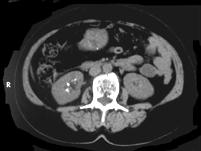

问题 女,26岁,右腰部不适2年,影像检查如图所示,应诊断为 ( )

选项 A、右侧慢性肾小管酸中毒 B、维生素D中毒所致的右肾改变 C、右肾结核瘤 D、甲旁亢所致的右肾改变 E、右侧髓质海绵肾

答案 E